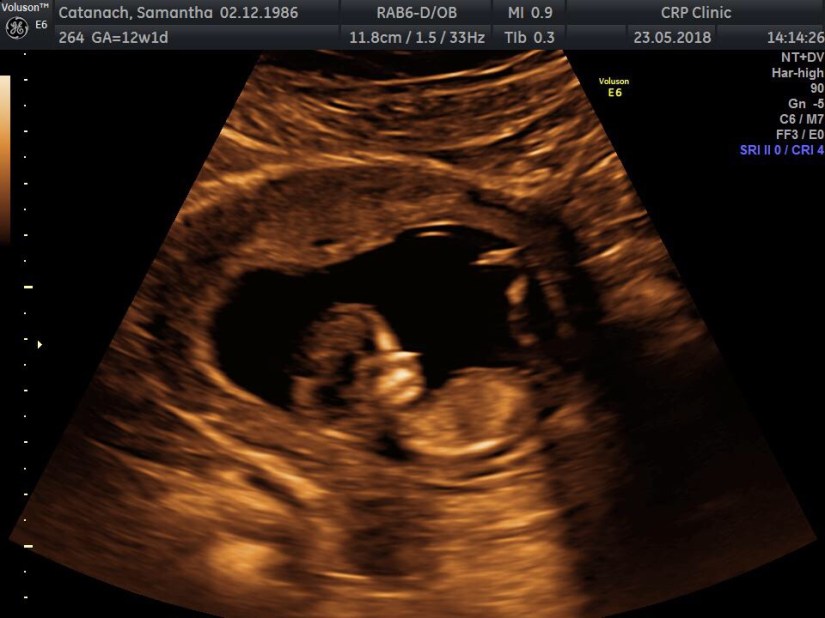

The following week we travelled to London for the biggest appointment so far, we had a 12 week nuchal scan with a specialist professor and it was time for my third dose of intralipids. The scan was just amazing and the professor was probably the most intelligent guy I have ever met, it lasted two full hours and he checked every single organ of our precious baby and the blood and oxygen flow through each of them too.

He was able to confirm that baby doesn’t have a cleft lip which was one of my concerns as it is a possible side effect of taking steroids in pregnancy. He also paid extra attention to babies bladder and so far it looks like it’s functioning normally and do hopefully baby won’t be born with a small capacity bladder like myself.

There was a realisation that it’s really happening at this point, more so for my husband I think, because it really looked like a baby and not this tiny blob any more! We got over 100 images from the scan and I’ll cherish them forever! Intralipid was also fine that day, I was used to it now and I was lucky enough to meet a lovely lady and we sat and chatted whilst having our treatment. She already had a little boy with help from the clinic and was now 16 weeks with baby number two!

The professor said that from this point, even though I wasn’t discharged and still needing treatment it would be highly unlikely that if this pregnancy was to end that it would be for the same reason as the other four. We travelled home that night with the most hope we have ever had, I had taken my laptop with us so that we could look at the photos on the train back, I just can’t believe there’s an actual baby.